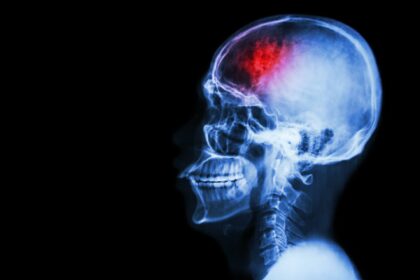

Kategoria zaburzeń i chorób neurologicznych obejmuje wszelkie nieprawidłowości w działaniu ośrodkowego i obwodowego układu nerwowego, które mogą być wrodzone lub nabyte. Bywają konsekwencją wypadku bądź naturalnych zmian, zachodzących np. w związku z podeszłym wiekiem. Występują zarówno u dzieci, jak i u osób dorosłych.

Układ nerwowy (składający się z ośrodkowego i obwodowego układu nerwowego) kontroluje pracę właściwie całego ludzkiego organizmu. To jego prawidłowa praca odpowiada za to, że poruszamy się, mamy sprawnie funkcjonującą pamięć, logicznie myślimy i wyciągamy wnioski, odbieramy bodźce ze świata zewnętrznego czy porozumiewamy się z innymi za pomocą mowy. W przypadku zaburzeń czynności układu nerwowego Pacjent może doświadczać wielu groźnych objawów, schorzenia neurologiczne mogą też być nawet powodem trwałego kalectwa lub niepełnosprawności. Z tego powodu przy wystąpieniu pierwszych objawów jak najszybciej należy udać się na konsultację lekarską. Odpowiednio wcześnie podjęta terapia ma szansę znacząco złagodzić skutki problemu bądź opóźnić rozwój choroby. Niektóre z chorób można nawet całkowicie wyleczyć.

Schorzenia układu nerwowego dzieli się na kategorie w zależności od ich podłoża: mogą to być zaburzenia genetyczne (wrodzone), immunologiczne, neurodegeneracyjne, naczyniowe, neuropatie bądź choroby neurologiczne o złożonej etiologii.

Z neurologiem i neuropsychologiem należy też oczywiście skonsultować się w przypadku wystąpienia udaru, doznania ataku padaczki lub zdiagnozowania u seniora choroby Alzheimera bądź innego zespołu otępiennego. Do specjalisty powinni przyjść też Pacjenci po urazach czaszkowo-mózgowych i po operacjach neurochirurgicznych np. z powodu guza mózgu.

Choroby neurologiczne diagnozowane są przez lekarza neurologa. Ten sam specjalista zajmuje się też leczeniem chorób neurologicznych. W zależności od rodzaju doznanego urazu bądź występujących objawów rozpoznaniu służy wywiad lekarski, badanie fizykalne i/lub takie badania jak EEG, USG wybranych obszarów ciała, badanie krwi i moczu, badanie laboratoryjne płynu mózgowo-rdzeniowego, tomografia komputerowa bądź rezonans magnetyczny. Po uzyskaniu diagnozy, oprócz podjęcia leczenia zaleconego przez neurologa, warto umówić się na konsultację neuropsychologiczną.